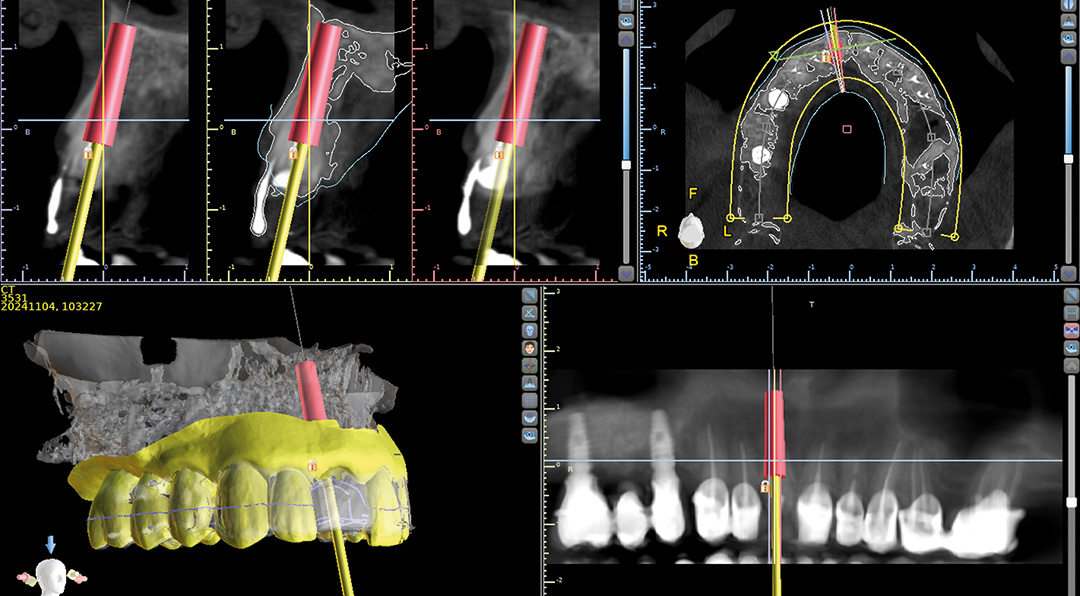

A CBCT and intraoral scans assessed the site, and coDiagnostiX® software was used to plan implant positioning and design the surgical guide virtually. The plan included immediate implant placement, filling the buccal gap with a xenograft and a soft tissue graft from the maxillary tuberosity to enhance soft tissue thickness in this high-risk aesthetic area.

An intraoral scan and a CBCT image were acquired as part of the comprehensive assessment. The images were matched using dental Blue Sky Bio software to facilitate the design of the surgical guide, using a prosthetically-driven planning approach to find the ideal 3D position of the implant. The surgical template was 3D printed and sterilised in preparation for surgery.